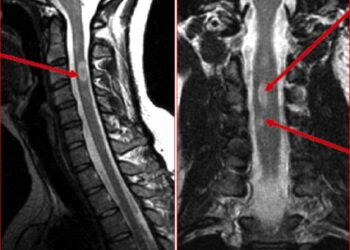

ЧИТАТЬ ВСЕДанные нового исследования показали, что большая потеря миелина — защитного покрытия вокруг нервных волокон — в части спинного мозга, расположенной в области...